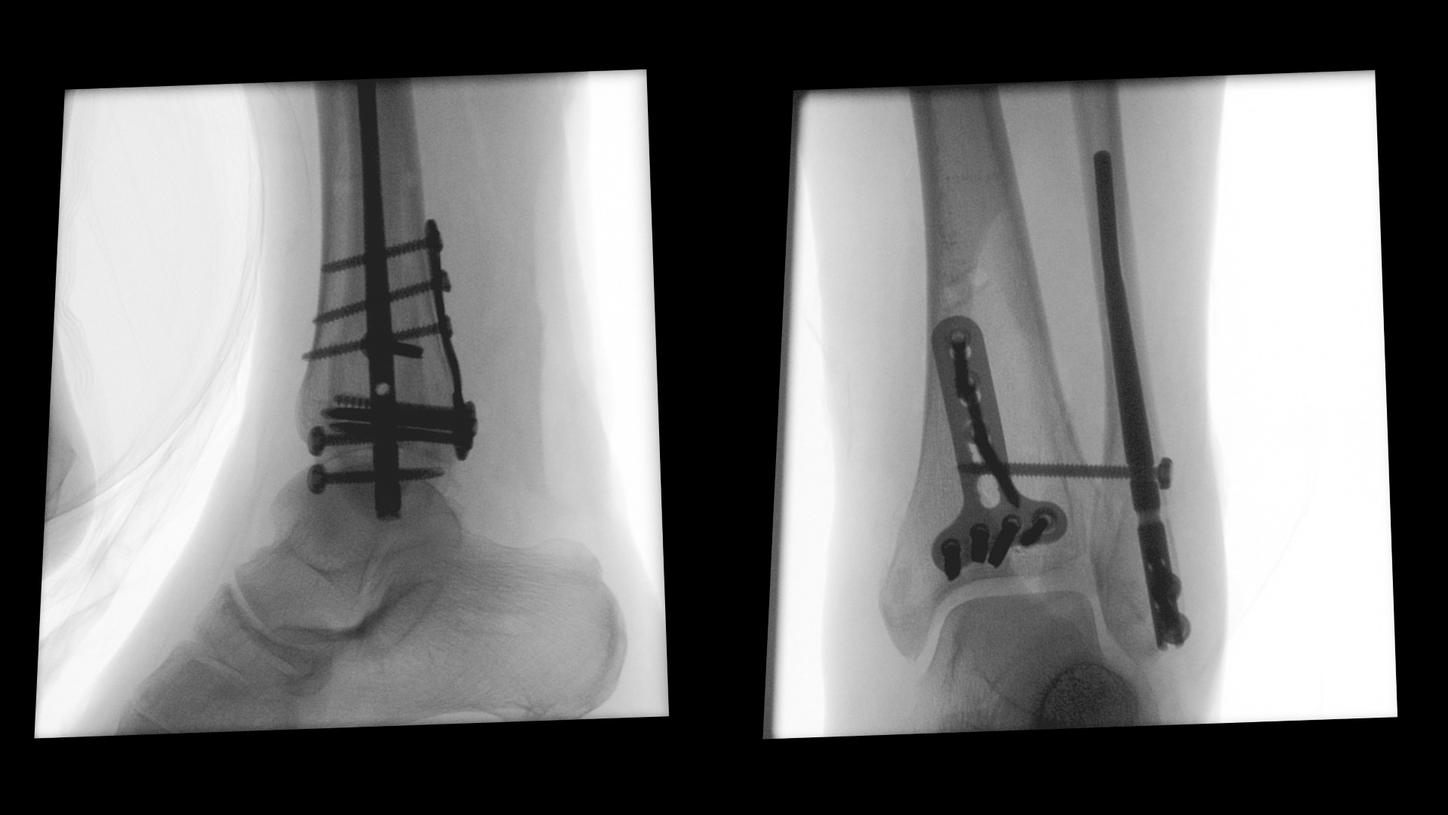

Benefit from precise 2D and 3D visualization of anatomical structures and metallic objects with excellent image quality.

Benefits for orthopedic and trauma surgery